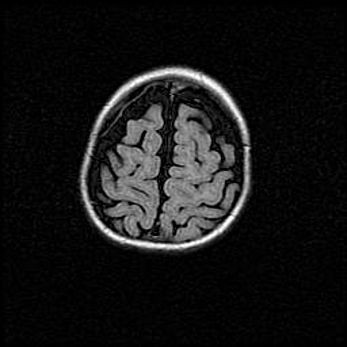

Церебральная ишемия II.

Возраст: 5 дней

Вес: 3400 г

Пол: женский

Окружность головы: 35 см

Срок гестации: 39 недель

Церебральная ишемия – это заболевание, характеризующееся недостаточностью (гипоксией) либо полным прекращением (аноксией) снабжения мозга кислородом по причине закупорки одного или нескольких сосудов. Это приводит к  что метаболическим расстройствам различной степени тяжести в тканях головного мозга, развитию коагуляционных некрозов и гибели нейронов.